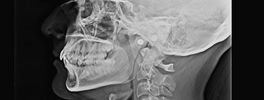

CEPHALOGRAM